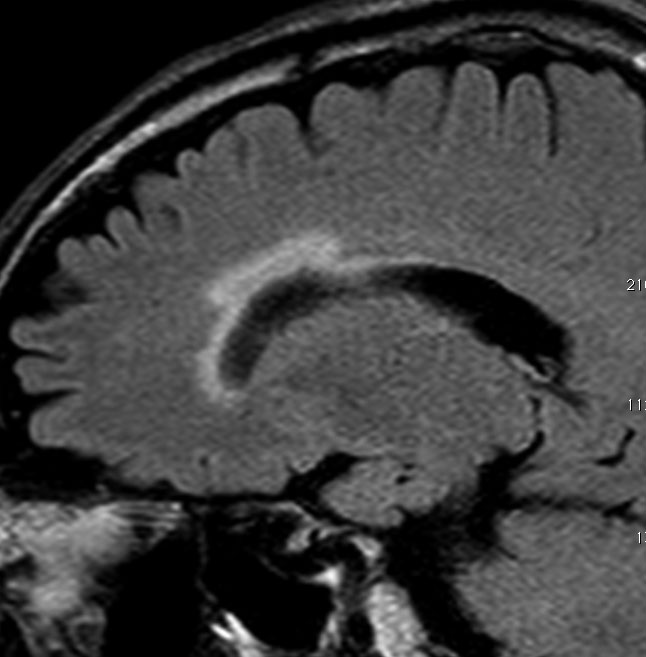

全脳照射でなくても局所照射でも放射線治療後には白質変性が生じます。無症状のことが多いですが,照射野内の脳萎縮などを伴うと高次脳機能障害などの症状をだすことはあります。

この患者さんは右前頭葉のびまん性星細胞腫に46グレイ23分割という低い線量の局所照射をしました。放射線治療8年後のMRI FLAIR画像です。腫瘍の再燃はなく,脳室周囲の白質が高信号になっています。脳梁や透明中隔の白質組織も高信号になり,非常に軽度の白質変性を示しています。でも,何の症状もありません。注意しなければならないのは,この所見を星細胞腫の再発あるいは進行と捉えて余分な治療をしないようにすることです。とくにグレード2の星細胞腫と乏突起膠腫の時に問題となります。